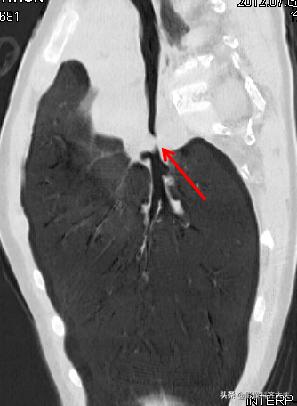

进行MPR(多平面重组)冠状位重建,清晰显示左侧左侧支气管有异物。

最小密度投影重建对于异物的显示更加清晰,红色箭头所示。